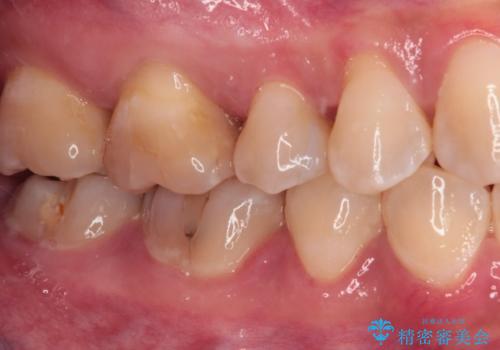

治療後は物が挟まることもなく、フロスが引っかかったり出血したりすることが減りました。